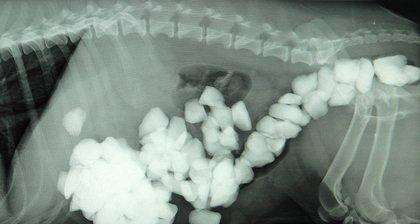

主人们尽量给狗狗挑选一些较大且结实的玩具,缝衣针和别针等则应收拾在一起。狗狗很容易将石块、骨头块、袜子、钥匙、毛球、金属、塑料袋等不能消化食用的物体当成食物吞入胃中,它们既不能被胃液所消化,又不能通过呕吐或经肠道排除体外,成为胃内异物,造成胃功能的紊乱,继发慢性胃炎等疾病。狗狗胃内异物与胃肠炎及犬细小病毒病在症状上很相似,如果不引起重视或者没有及时准确找出病因进行治疗,很容易威胁狗狗的生命。